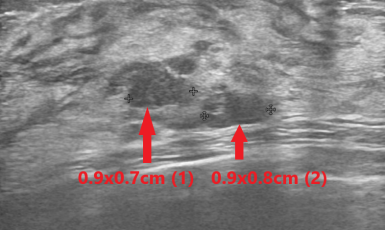

308번째 갑상선암 진단사례 (2019년8월27일) 왼쪽 가슴이 아파서 유방 초음파 검사위해 내원한 환자분이셨습니다. 유방 초음파상에서는 양쪽에 양성으로 보이는 다발성 결절들..